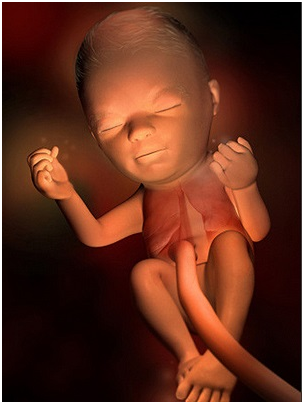

怀孕第14周祝贺你,你的肚肚就要显露出来了!宝宝身体的所有基本构造也已经形成,尽管它们很小,...

怀孕第14周祝贺你,你的肚肚就要显露出来了!宝宝身体的所有基本构造也已经形成,尽管它们很小,... -

怀孕第15周现在你需要做一次产前诊断了,15~18周之间是做产前诊断的最佳时期;怀孕改变了你...

怀孕第15周现在你需要做一次产前诊断了,15~18周之间是做产前诊断的最佳时期;怀孕改变了你... -

怀孕第12周现在胎儿身体的雏形已经发育完成了,你的脸和脖子上可能会不同程度地出现黄褐斑,腹部...

怀孕第12周现在胎儿身体的雏形已经发育完成了,你的脸和脖子上可能会不同程度地出现黄褐斑,腹部... -

怀孕第13周胎儿脸部更加清晰了,肚子开始变大,妊娠趋于稳定,妊娠反应消失,食欲也很不错。这时...

怀孕第13周胎儿脸部更加清晰了,肚子开始变大,妊娠趋于稳定,妊娠反应消失,食欲也很不错。这时... -